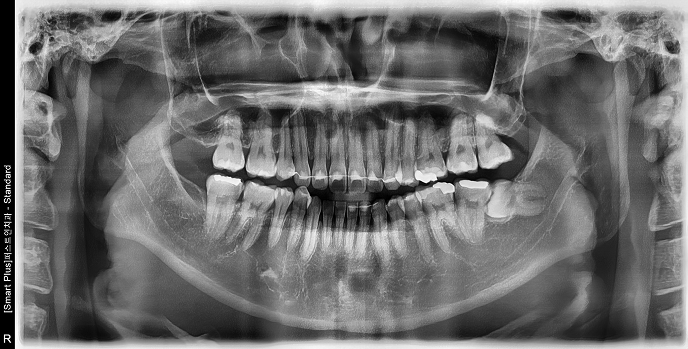

• 30대 여성 | #38 사랑니발치 | 치료기간 당일

Before 2025.03.06

After 2025.03.06